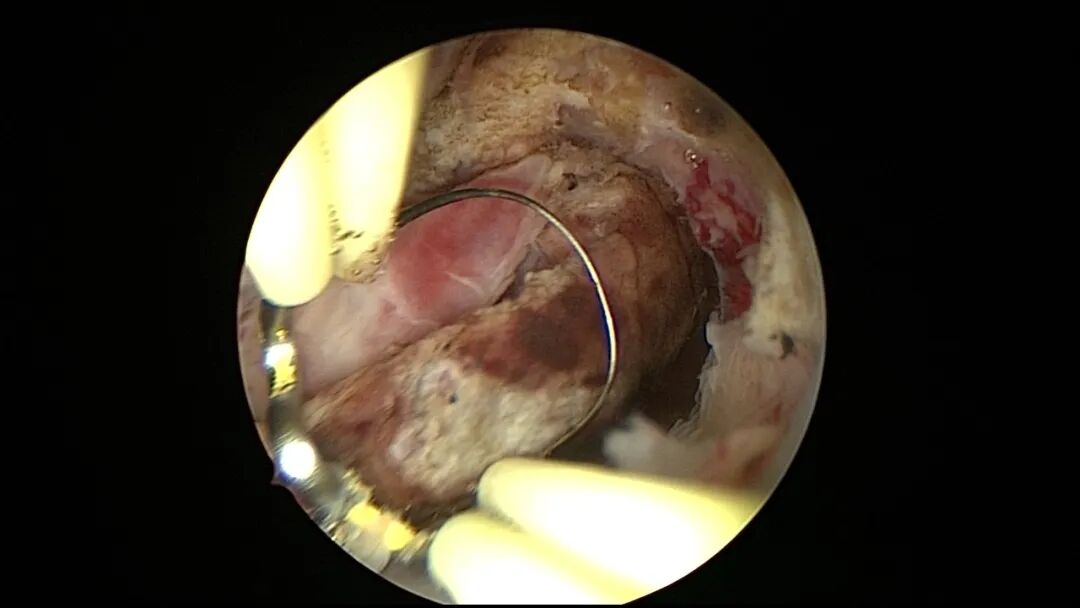

第六次宫腔镜:2024年2月自然妊娠10周,2024年4月初妊娠3+月(BPD2.6cm),坚决要求终止妊娠,行宫腔镜辅助终止妊娠。门诊医生给与米非司酮片及米索前列醇口服3天,胚胎掉出后行宫腔镜辅助下清宫,确保无胚物残留,术前宫深11.5cm,术后宫深10cm。